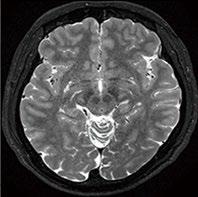

PD STIR - 1024 x 1024 matrix - 3mm slice thickness

Sag T2 - 0.5 x 0.5 min - 0:56 min Ax PD FatSat - 0.6 x 0.6 mm - 1:30 min Cor PD FatSat - 0.6 x 0.6 mm - 1:15 min Cor PD - 0.5 x 0.5 mm - 0:58 min © 2020 CANON MEDICAL SYSTEMS // MREU200040

Fast knee protocol with AiCE on Vantage Orian 1.5T